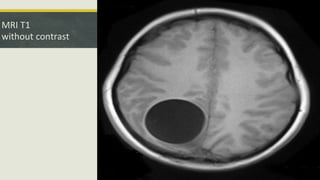

MRI T1

without contrast

• #17 Axial T1 sequence without contrast Intra axial lesion in the right parietal lobe that confirms the cystic nature of this lesion because of its signal characteristics which is very similar to that of the CSF. well defined. some hypo-intensity within the adjacent brain parenchyma in the parasagittal occipital lobe which suggests a vasogenic edema no apparent soft tissue component.